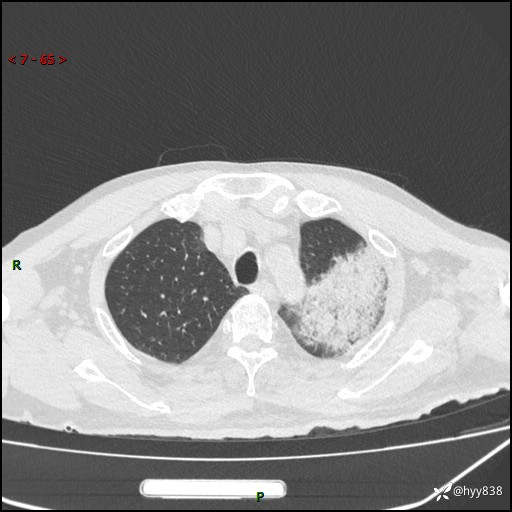

胸部CT复查(2024.8.5)